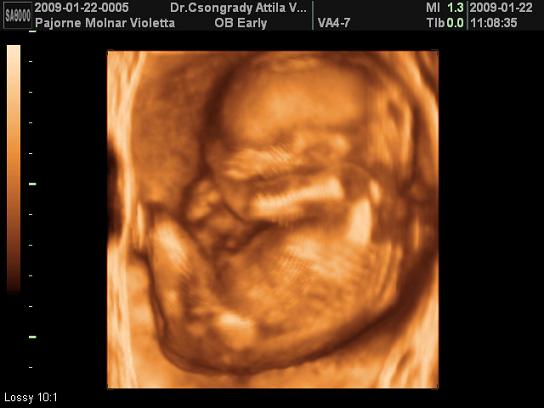

TEgnap voltam UH-n, mindjárt mutatok képet. Sajna Levente elég rossz néven vette, hogy zargatjuk, ahogy tudta takarta magát. Így nem sokat láttunk belőle, de azt megosztom Veletek.

Vivi, még csak most jelentetted be, hogy kisbabát vársz és már félidőnél tartasz. Nem semmi. Szépséges Levente, milyen szépen megmutatta magát! Nagyon klassz felvételek.